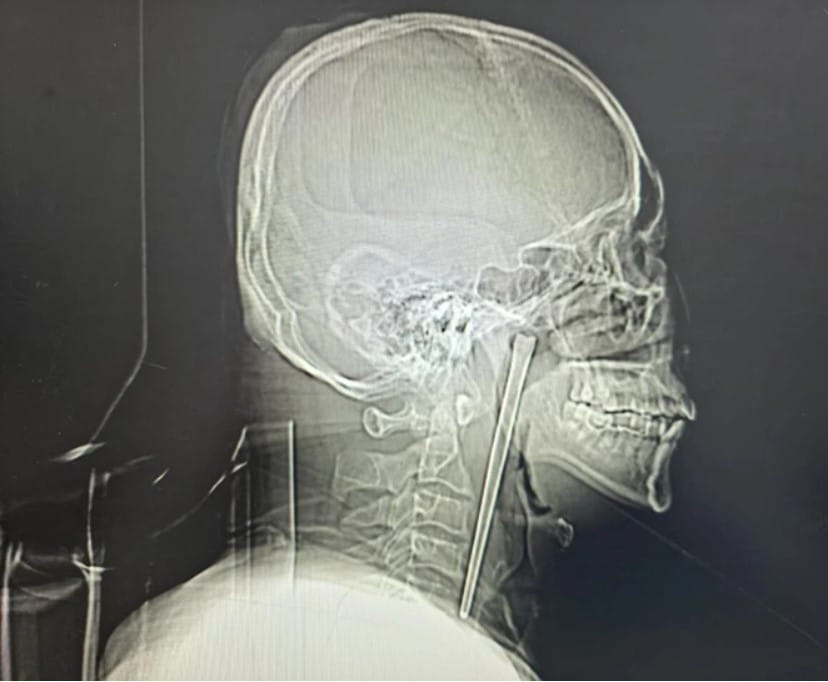

Yapılan incelemelerde adamın boğazında tam 12 santimetre uzunluğunda metal bir yemek çubuğu olduğu saptandı. İşin en sarsıcı yanı ise bu yabancı cismin tam 8 yıldır orada olduğunun ortaya çıkmasıydı.

Geçen yılların ardından ağrıların dayanılmaz hale gelmesi ve kanama riskinin artması üzerine uzman cerrahlar devreye girdi. Oddıtycentral haberine göre, boyun bölgesine dışarıdan müdahale edilmesini istemeyen hastanın talebi üzerine Dr. Huang Weipeng ve ekibi ağız içinden gerçekleştirilen özel bir yöntem geliştirdi.

12 santimetrelik paslanmaz çelik çubuk dokulara daha fazla zarar vermeden büyük bir titizlikle vücuttan tahliye edildi.